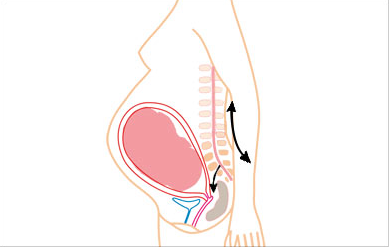

Gravidez e dores nas costas

As dores nas costas correspondem à complicação mais comum da gravidez. Vários estudos relataram que mais de 50% sofrem com problemas nas costas durante os 9 meses de gravidez, sendo que 75% não tinham histórico de dores lombares...